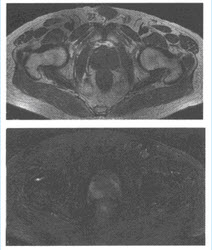

(单选题)患者做MRI检查如下图,最可能的诊断是()

A:前列腺增生

B:前列腺癌

C:前列腺肉瘤

D:前列腺囊肿

E:前列腺炎

F:前列腺囊性腺瘤